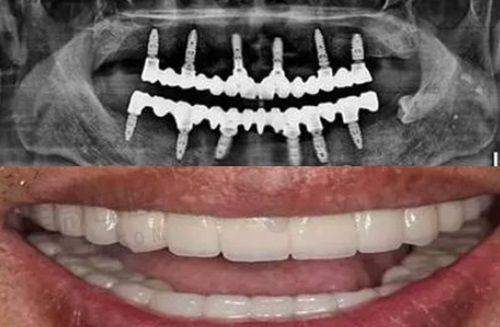

3. 看“真实实例”,别信“明星p图” 深圳特别多医院展示“明星实例”,但这些可能是p的。一定要看“和你情况类似的实例”,比如你是“地包天”,就看医生做过的“地包天”实例,看术后的“面部变化”“咬合情况”“修复时间”——真实实例才能帮你判断“成效好不好”!